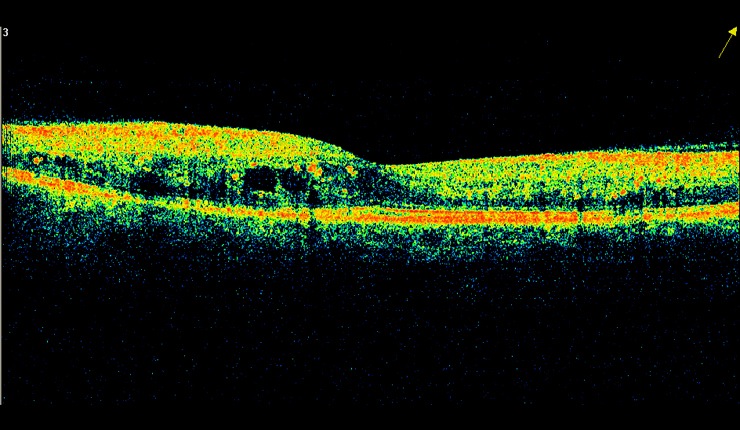

OCT radial scan display showing arcade pattern of fluid associated with branch retinal vein occlusion.